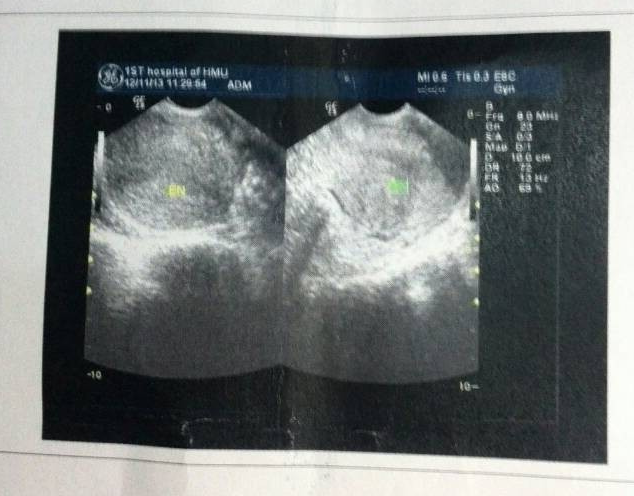

病情分析: 根据您上述描述的情况不知道您去看病的分别是什么医院?我考虑上述的情况我也考虑多囊卵巢综合征。 指导意见: 不知道您现在月经推迟了几天呀?建议您进一步补充上述的问题,希望能够更好的帮助到您。